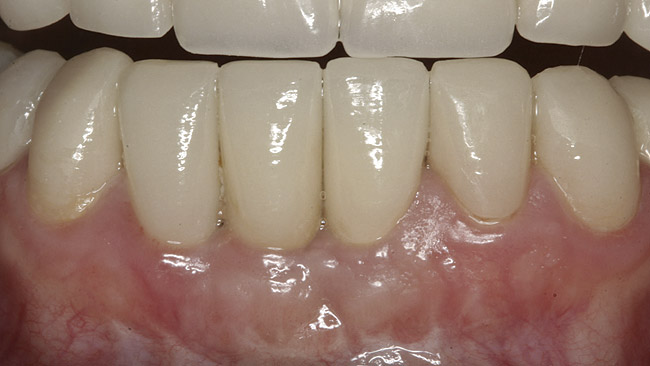

After the zirconia abutments were torqued to 20 Ncm, cotton and composite were used to cover the screw access openings. Figure 7 and Figure 8 show the finished feldspathic porcelain crowns on implants in sites Nos. 24 through 26, and on teeth Nos. 22, 23, 27, and 28; all crowns were cemented with dual-cure resin cement. Good remodeling of gingival architecture is also apparent in Figure 7. As predicted, the free gingival margin (FGM) on No. 23 is approximately 2 mm coronal to those of the adjacent implant crowns on Nos. 24 through 26 (Figure 7); as per the patient’s initial statement, this discrepancy was not an esthetic concern to her. Figure 9 shows the final post-restoration periapical view.

This patient faced a unique situation, perhaps not previously reported: retaining a healthy mandibular lateral incisor knowing this would create an esthetic compromise. Indeed, while the discrepancy in gingival-margin height is noticeable in retracted view (Figure 7), it does not show in full smile (Figure 8).

Figure 7  Finished feldspathic crowns, teeth Nos. 22, 23, 27, 28, and implant sites 24 through 26 showing good gingival emergence profile—post-cementation facial view.

Figure 7

Figure 8  Full smile—finished feldspathic crowns on teeth Nos. 22, 23, 27, and 28; implant crowns in sites 24 through 26; esthetic harmonization with opposing dentition.

Figure 8